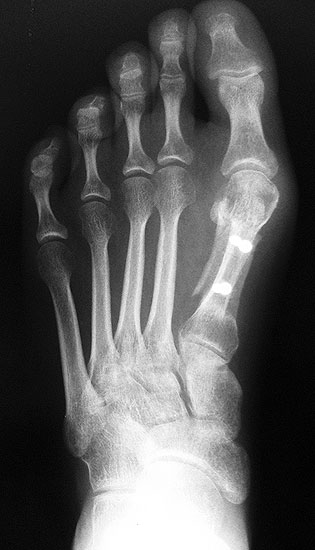

2) Rezidiv bei insuffizienter operativer Technik:

Die dorsoplantaren Röntgenaufnahmen zeigen eine Open-wedge Technik mit der normalerweise ein erhöhter intermetatarsaler Winkel gut zu korrigieren ist (Abbildung 3). Die Wirksamkeit einer Basisosteotomie ist umso größer, je proximaler diese durchgeführt wird. Je weiter distal die Osteotomie, umso geringer die Korrektur. Auf den postoperativen Bildern ist der distal unverändert große Abstand zwischen Metatarsale I und Metatarsale II erkennbar, bei gleichzeitiger Subluxation des Großzehengrundgelenks und dezentrierten Sesambeinen. Darüber hinaus finden sich initiale degenerative Veränderungen im Großzehengrundgelenk. Klinisch bestand eine hohe Weichteilspannung, bei verkürzter Extensor- und Flexor hallucis longus Sehne.  Daher wurde ein verkürzendes Verfahren zur Revision gewählt (Abbildung 4). Die Lapidusarthrodese stellt ein sehr zuverlässiges Verfahren zur Behandlung von Hallux valgus Rezidiven dar 9. Die Fusion des Tarsometatarsale-I-Gelenks kombiniert Stabilität mit einem hohen Korrekturpotenzial. Aufgrund der verfahrensimmanenten Verkürzung des ersten Strahls und der in diesem Fall bereits präoperativ vorhandenen Transfermetatarsalgie wurde die Entscheidung für eine verkürzte Weil-Osteotomie am zweiten bis fünften Strahl gefällt. Die Kombination beider Verfahren führte zu einem homogenen Metatarsale-Index und zu einer gleichmäßigen plantaren Druckverteilung 10. Die Hallux valgus interphalangeus Fehlstellung wurde mit einer Akin-Osteotomie korrigiert.